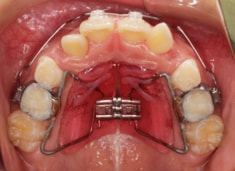

治療法:上顎急速拡大装置+クリアスナップ+フェイスマスク+上顎3番は開窓牽引CT写真にて位置確認

治療前

治療開始時